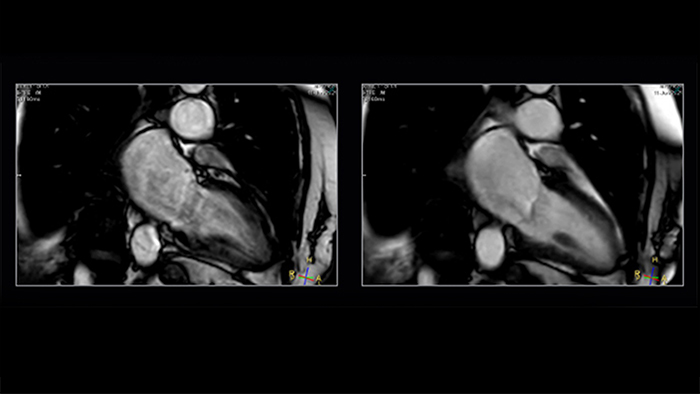

Shorter data readouts [2] enabled by Compressed SENSE provide benefit for black bloods and T1 mapping as well with sharper images acquired. For T1 mapping this results in fewer unconfident pixels on the resulting T1 map (see Fig. 3).

Figure 3. T1 mapping: shorter readouts using C-SENSE x3 leads to fewer unconfident pixels. Left to right: SENSE x2, C-SENSE x3